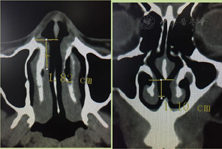

体检及检查:入院常规内科查体无异常发现。鼻内镜下见:双侧鼻腔欠通畅,双下鼻甲肥大,鼻中隔无明显偏曲,鼻中隔中前方可见1.5cm×1.0cm左右大穿孔。间接喉镜下见:右侧声带充血明显,见新生物生长,表面不光滑,基底广泛,对侧声带明显充血水肿,声门开闭尚。电子喉镜检查诊断"鼻中隔穿孔、右侧声带息肉";鼻部CT提示鼻中隔穿孔(图1)。已排除梅毒、外伤等其他引起鼻中隔穿孔原因。